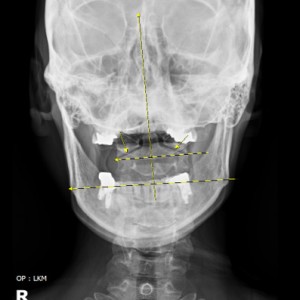

전신 엑스레이 검사

턱, 어깨 높이, 골반 틀어짐, 부정렬

턱관절 검사에 전신 척추를 촬영·검사하는 이유가 무엇인가요?

턱관절과 척추가 신체 정렬과 기능에 밀접하게 연결되어 있기 때문입니다. 턱관절 문제는 목뼈를 포함한 척추 정렬에 영향을 미치며, 이는 전신적인 불균형을 초래할 수 있습니다. 또한 턱관절과 척추는 근육 및 신경계를 통해 상호작용하므로, 턱관절 이상은 목과 어깨는 물론 척추 전체에도 연쇄적인 영향을 미칠 가능성이 있습니다. 전신 척추 촬영은 턱관절 문제의 정확한 원인을 파악하고, 자세와 정렬의 이상을 분석하여 근본적인 치료 전략을 세우기 위해 필수적입니다.